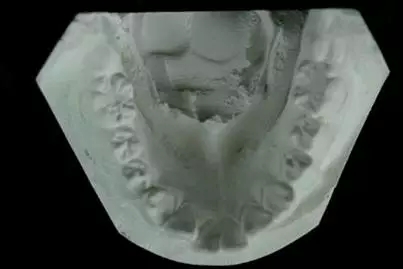

【口腔正畸】制作記存模型

(2) 評估和記錄牙體解剖形態(tài)

(3) 評估和記錄牙弓形態(tài)

(4) 記錄上,下頜牙齒的尖窩關系

(5) 評估和記錄<牙合>曲線